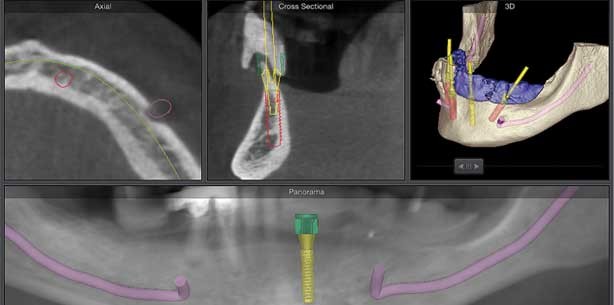

Im Unterkiefer wurde dem Patienten eine Planung mit divergierenden Implantaten nach dem Malo-Prinzip vorgestellt (Abb. 2). Die prothetische Unterstützungsfläche wird durch die schräge Implantatpositionierung nach distal ausgedehnt und der ortsständige Knochen so optimal ausgenutzt. Da noch eine Restbezahnung bestand, konnte nach 3-D-Darstellung des Unterkiefers auf eine zahngetragene Bohrschablonenplanung zurückgegriffen werden.

Die Sekundärteile für das angestrebte „Malo-Konzept“ sind mit einer Angulierung von 17° sowie 30° (Abb. 5) ­erhältlich, auch hier ist die Software eine große Hilfe, da die Implantatachsen exakt zueinander vermessen werden können (Abb. 6a und b). Bei der virtuellen Implantation in der Software wurde auch die Reihenfolge der zu setzenden Implantate festgelegt, da aufgrund der zu entfernenden Restbezahnung zwei Operationsschablonen für den Unterkiefer benötigt wurden, um zu jeder Zeit eine optimale Fixierung dieser zu gewährleisten. Nach der Definition des Tiefenanschlages des Hülsensystems gibt die Software die Koordinaten für den Techniker und ein OP-Protokoll aus.